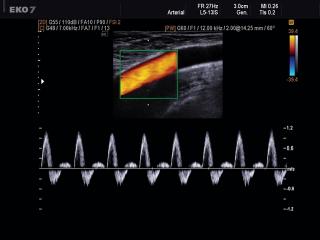

Common femoral artery, CFM & PW

EKO7. Common femoral artery, CFM & PW.